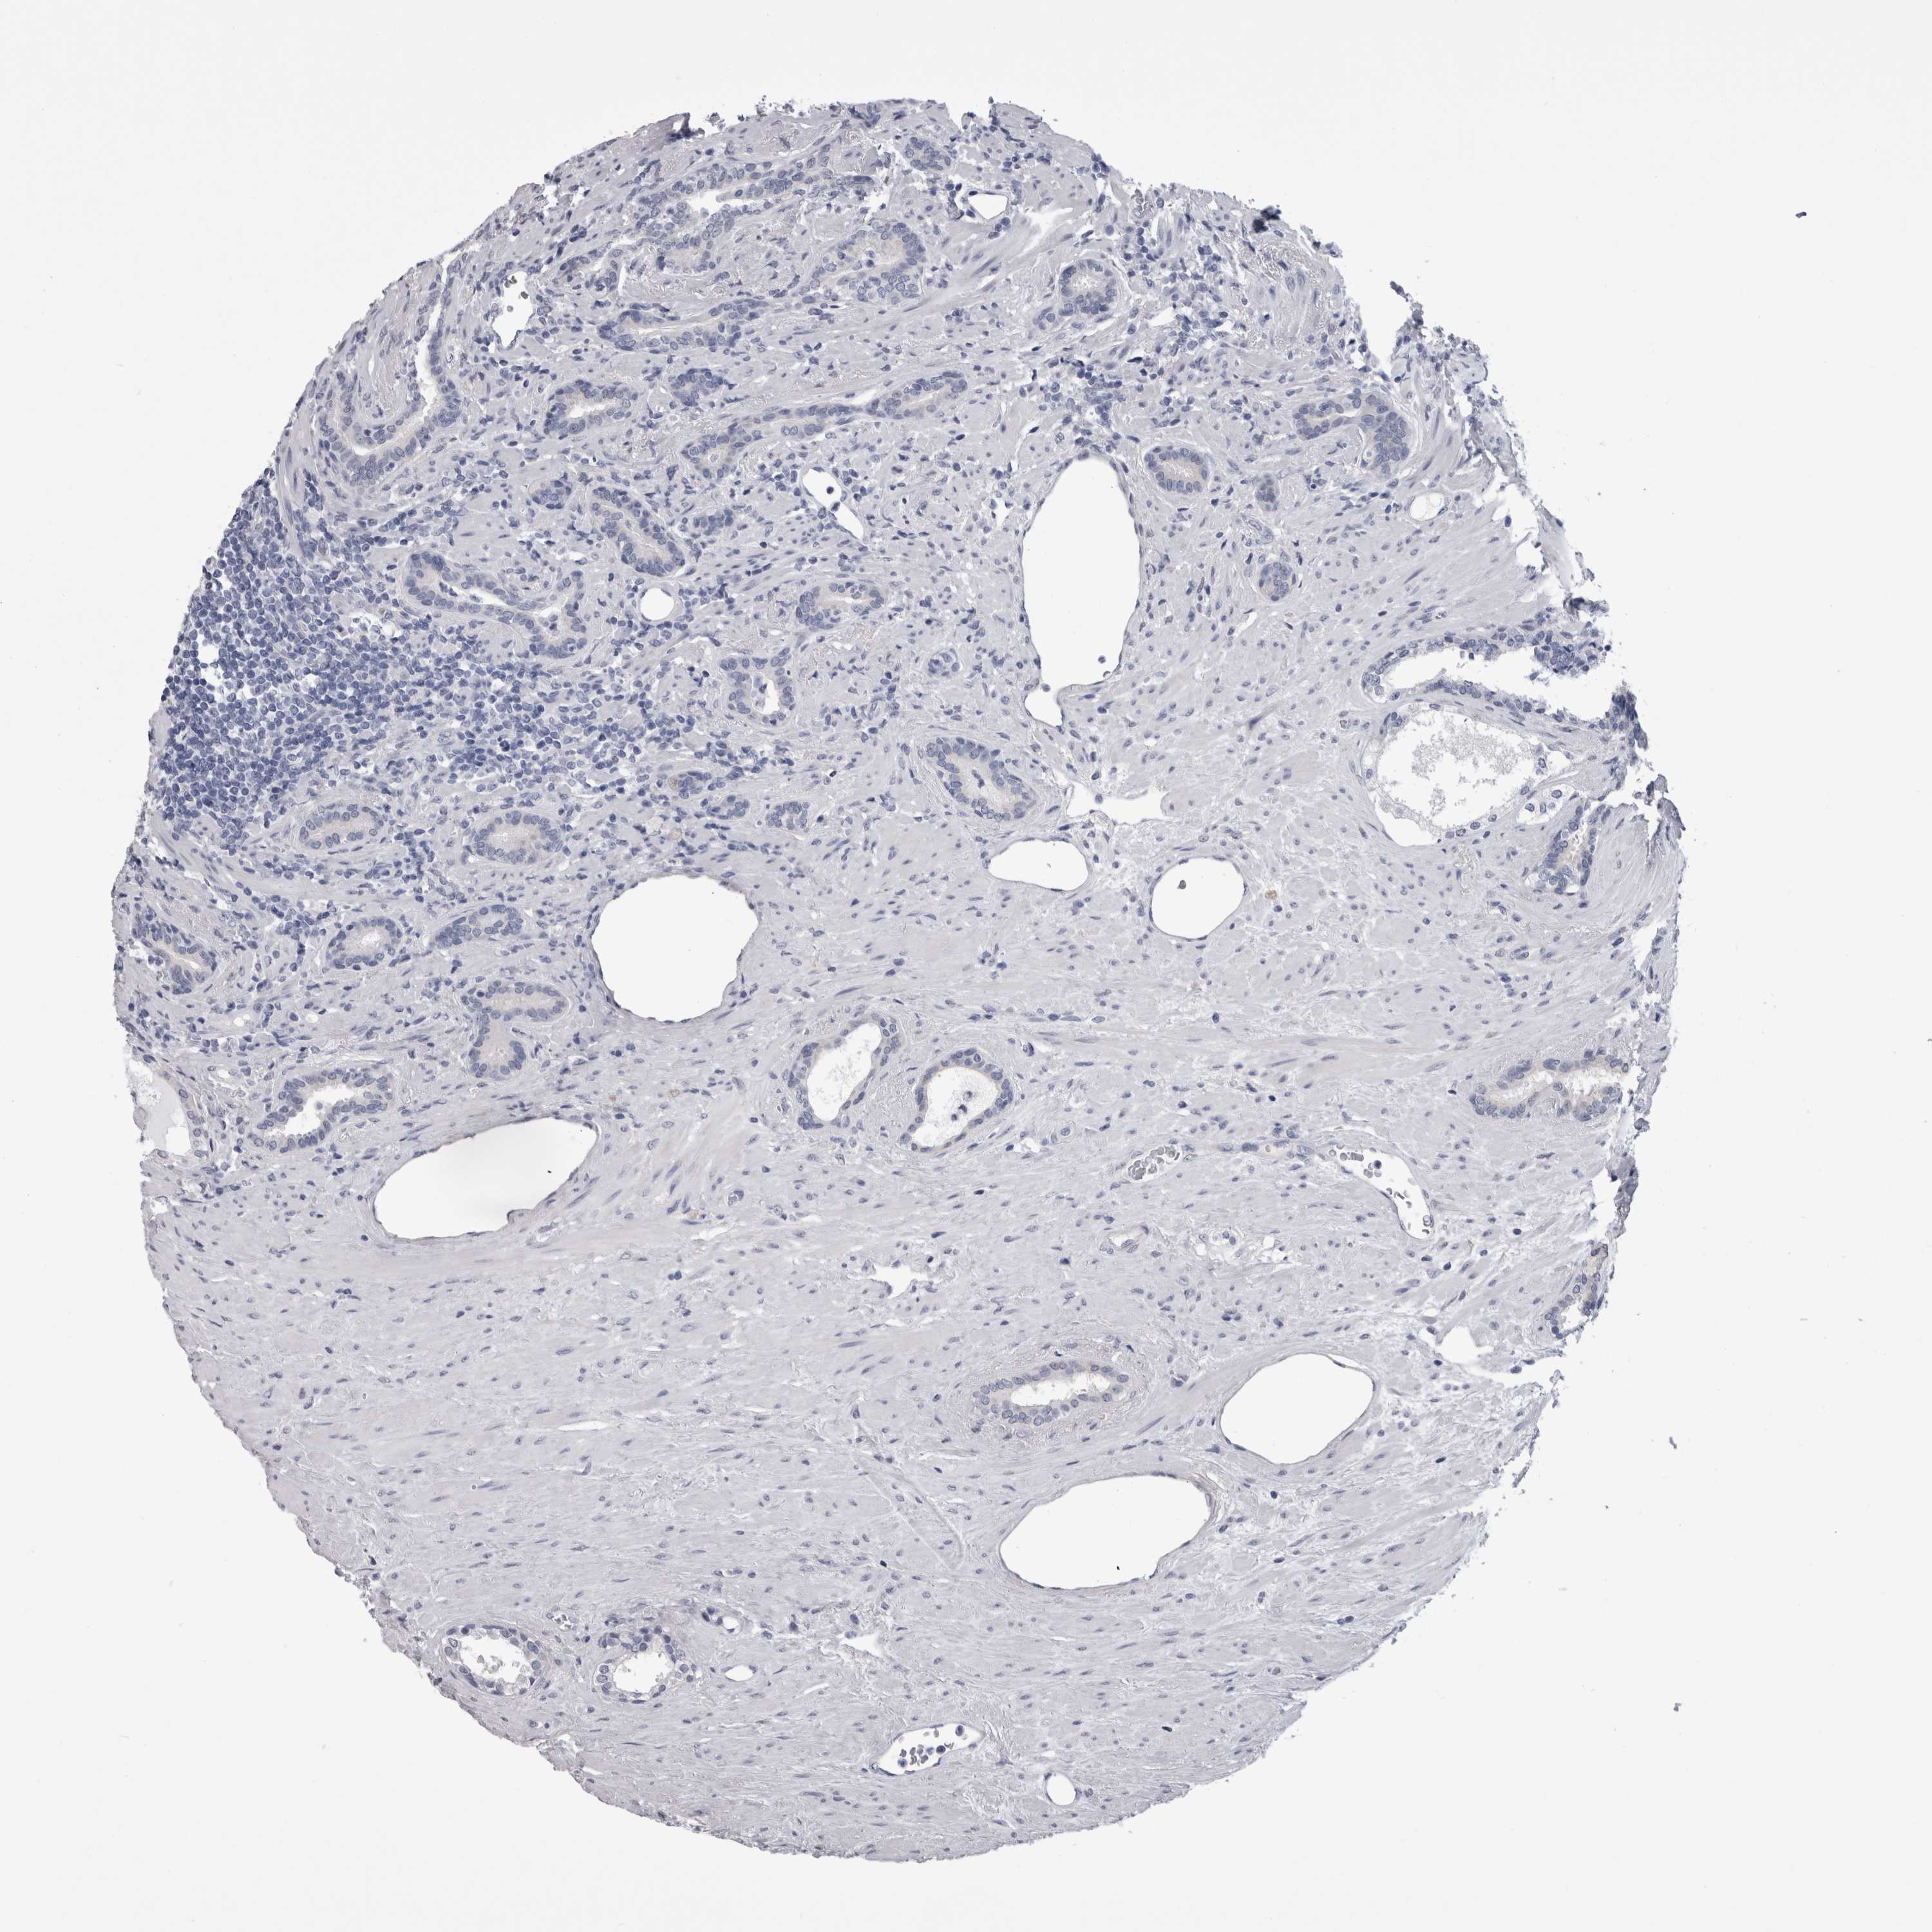

PROSTATE CANCER - Protein expressioni

A mouse-over function shows sample information and annotation data. Click on an image to view it in a full screen mode. Samples can be filtered based on level of antibody staining by selecting one or several of the following categories: high, medium, low and not detected. The assay and annotation is described here.

Note that samples used for immunohistochemistry by the Human Protein Atlas do not correspond to samples in the TCGA dataset.

Antibody stainingi

Antibody staining in the annotated cell types in the current human tissue is reported as not detected, low, medium, or high, based on conventional immunohistochemistry profiling in selected tissues. This score is based on the combination of the staining intensity and fraction of stained cells.

Each image is clickable and will lead to virtual microscopy that enables deeper exploration of all samples and also displays staining intensity scores, fraction scores and subcellular localization as well as patient and tissue information for each sample.

Antibody HPA023861

Antibody HPA026536

Staining

High

Medium

Low

Not detected

Intensity

Strong

Moderate

Weak

Negative

Quantity

>75%

75%-25%

<25%

None

Location

Nuclear

Cytoplasmic/membranous

Cytoplasmic/membranous,nuclear

Adenocarcinoma, High grade

Adenocarcinoma, Low grade